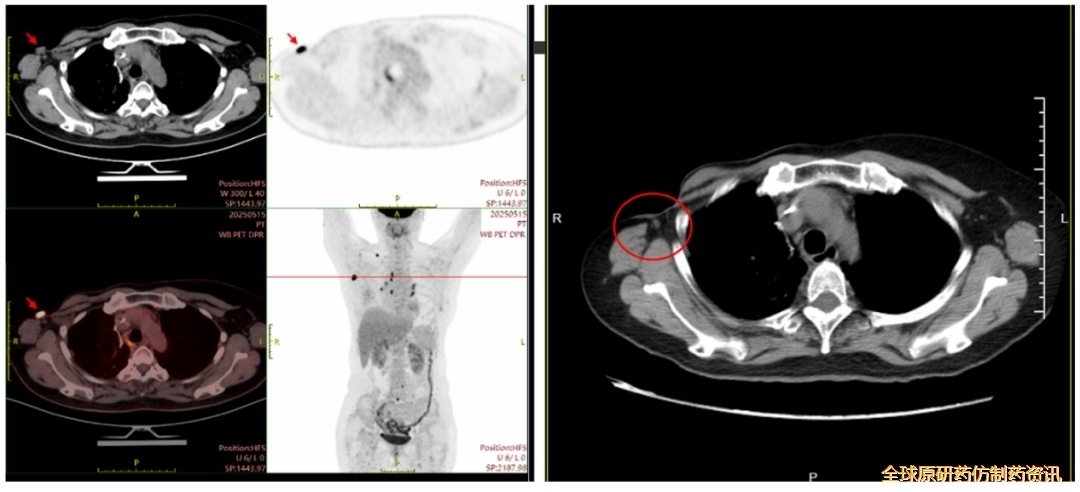

2025-5-15行PET-CT:

右乳术后复查:右侧胸壁术后改变;右侧腋窝结节(1.6*1.5cm),考虑转移或复发;右侧锁骨区散在淋巴结转移;b.右肺上叶术后改变;双肺多发小结节,FDG代谢未见增高,建议随诊;c.L4椎体及L5棘突FDG代谢增高,转移待排,建议结合增强MR检查或密切随诊。

图2 .患者疗效评估

(图左:PET-CT检查,时间2025-5-15;图右:胸部CT检查,时间2025-7-22)